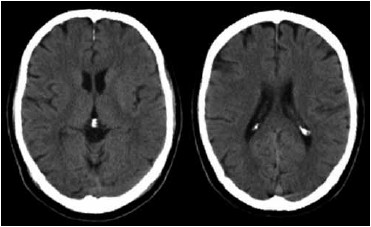

Paciente de 71 anos, masculino, hipertenso e diabético, admitido no pronto-socorro com hemiplegia completa à esquerda com 2 horas do início dos sintomas. Pontuação na escala do NIH de 8. Na admissão, pressão arterial de 180/90 mmHg, glicemia capilar 125 mg/dL, Sat02 em ar ambiente de 94%. Tomografia de crânio sem contraste exibida a seguir. Assinale a alternativa que apresenta corretamente a melhor conduta para este paciente.

(Arquivo pessoal; imagem usada com autorização)